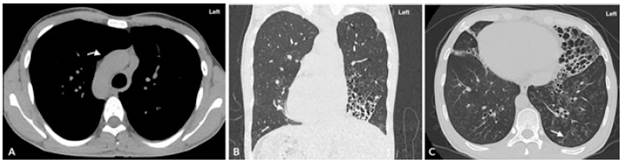

High-resolution computed tomography of the chest with isomerism of the bronchial branching pattern. A) coronal view of bi-lobed right lung; B) sagittal view of tri-lobed left lung.

Figure 2: High-resolution computed tomography of the chest with isomerism of the bronchial branching pattern. A) coronal view of bi-lobed right lung; B) sagittal view of tri-lobed left lung.

Source: Document obtained during the study.